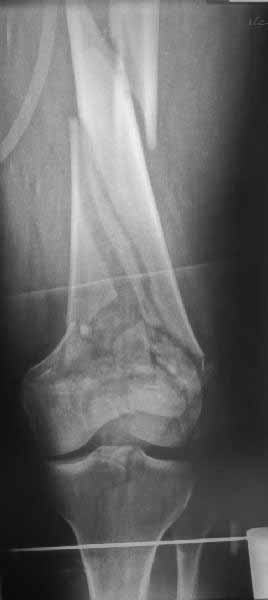

Однако в случае, представленном Константином Никитиным, не может быть применён ни ретроградный ни антеградный остеосинтез. Причина - нереально выполнить вышеуказанные необходимые требования, касающиеся дистальных блокирующих винтов. Из-за низкого перелома латерального мыщелка (перелом Hoffa) невозможно через него провести хотя бы 2 блокирующих винта, поскольку линия перелома мыщелка расположена либо на уровне верхушки межмыщелковой ямки либо незначительно проксимальнее. Поэтому авторам, с моей точки зрения, необходимо прислушаться к рекомендациям Джолдаса.

Ответ на эту часть Вашего поста – вложенный файл. Больная оперирована неделю назад по поводу открытого перелома дистального эпиметафиза бедренной кости. После операции она идёт в рентгенкабинет для выполнения послеоперационной контрольной рентгенографии, представленной на слайдах 10 и 11. Узнав, почему её фотографируют, просила передать Вам, Антон, привет.

наружный мыщелок не дорепонироавн - это приводит к вальгусной деформации оси коленного сустава, очень критично для последующей функции.